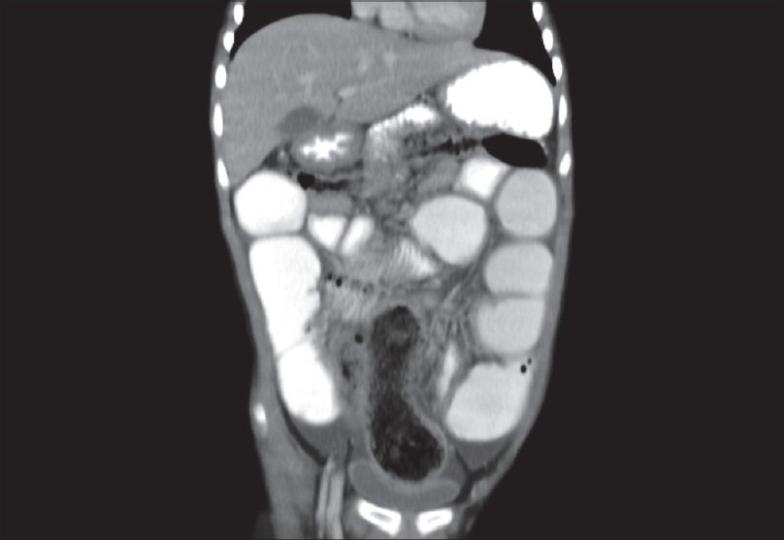

伴有穿孔的末端回肠毛粪石:一种罕见表现并文献复习

Terminal ileal trichophytobezoar with perforation: A rare presentation with review.

Trichophytobezoars are uncommon foreign bodies, formed by hairs and vegetable matter with impacted food particles. We report an unusual case of a 5-year-old girl with large terminal ileal trichophytobezoar causing perforation peritonitis.

摘要

毛发植物粪石是由毛发、植物物质和嵌塞的食物颗粒形成的罕见异物。我们报告了一例不寻常的病例,一名5岁女孩患有巨大的回肠末端毛发植物粪石,导致穿孔性腹膜炎。